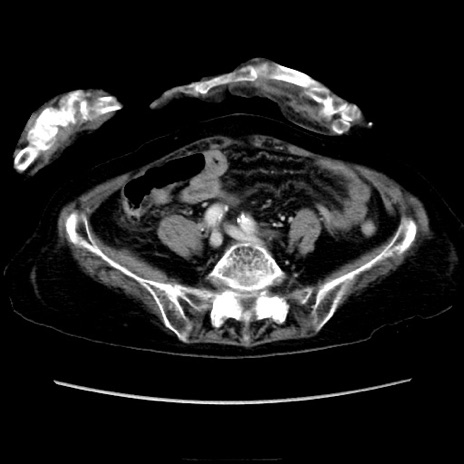

症例40(横断像)

【症例】90歳代女性

【主訴】腹痛・嘔吐

【現病歴】 食欲低下、嘔吐があり昨日他院受診。肺炎と診断され入院となる。入院後より腹部全体に圧痛あり。胃管留置され経過みていたが、症状持続するため、

当院転院となる。

【既往歴】胸椎圧迫骨折、胆石症

【身体所見】腹部:中央に激痛あり、圧痛あり、反跳痛不明

【データ】WBC 17100、CRP 18.82

横断像